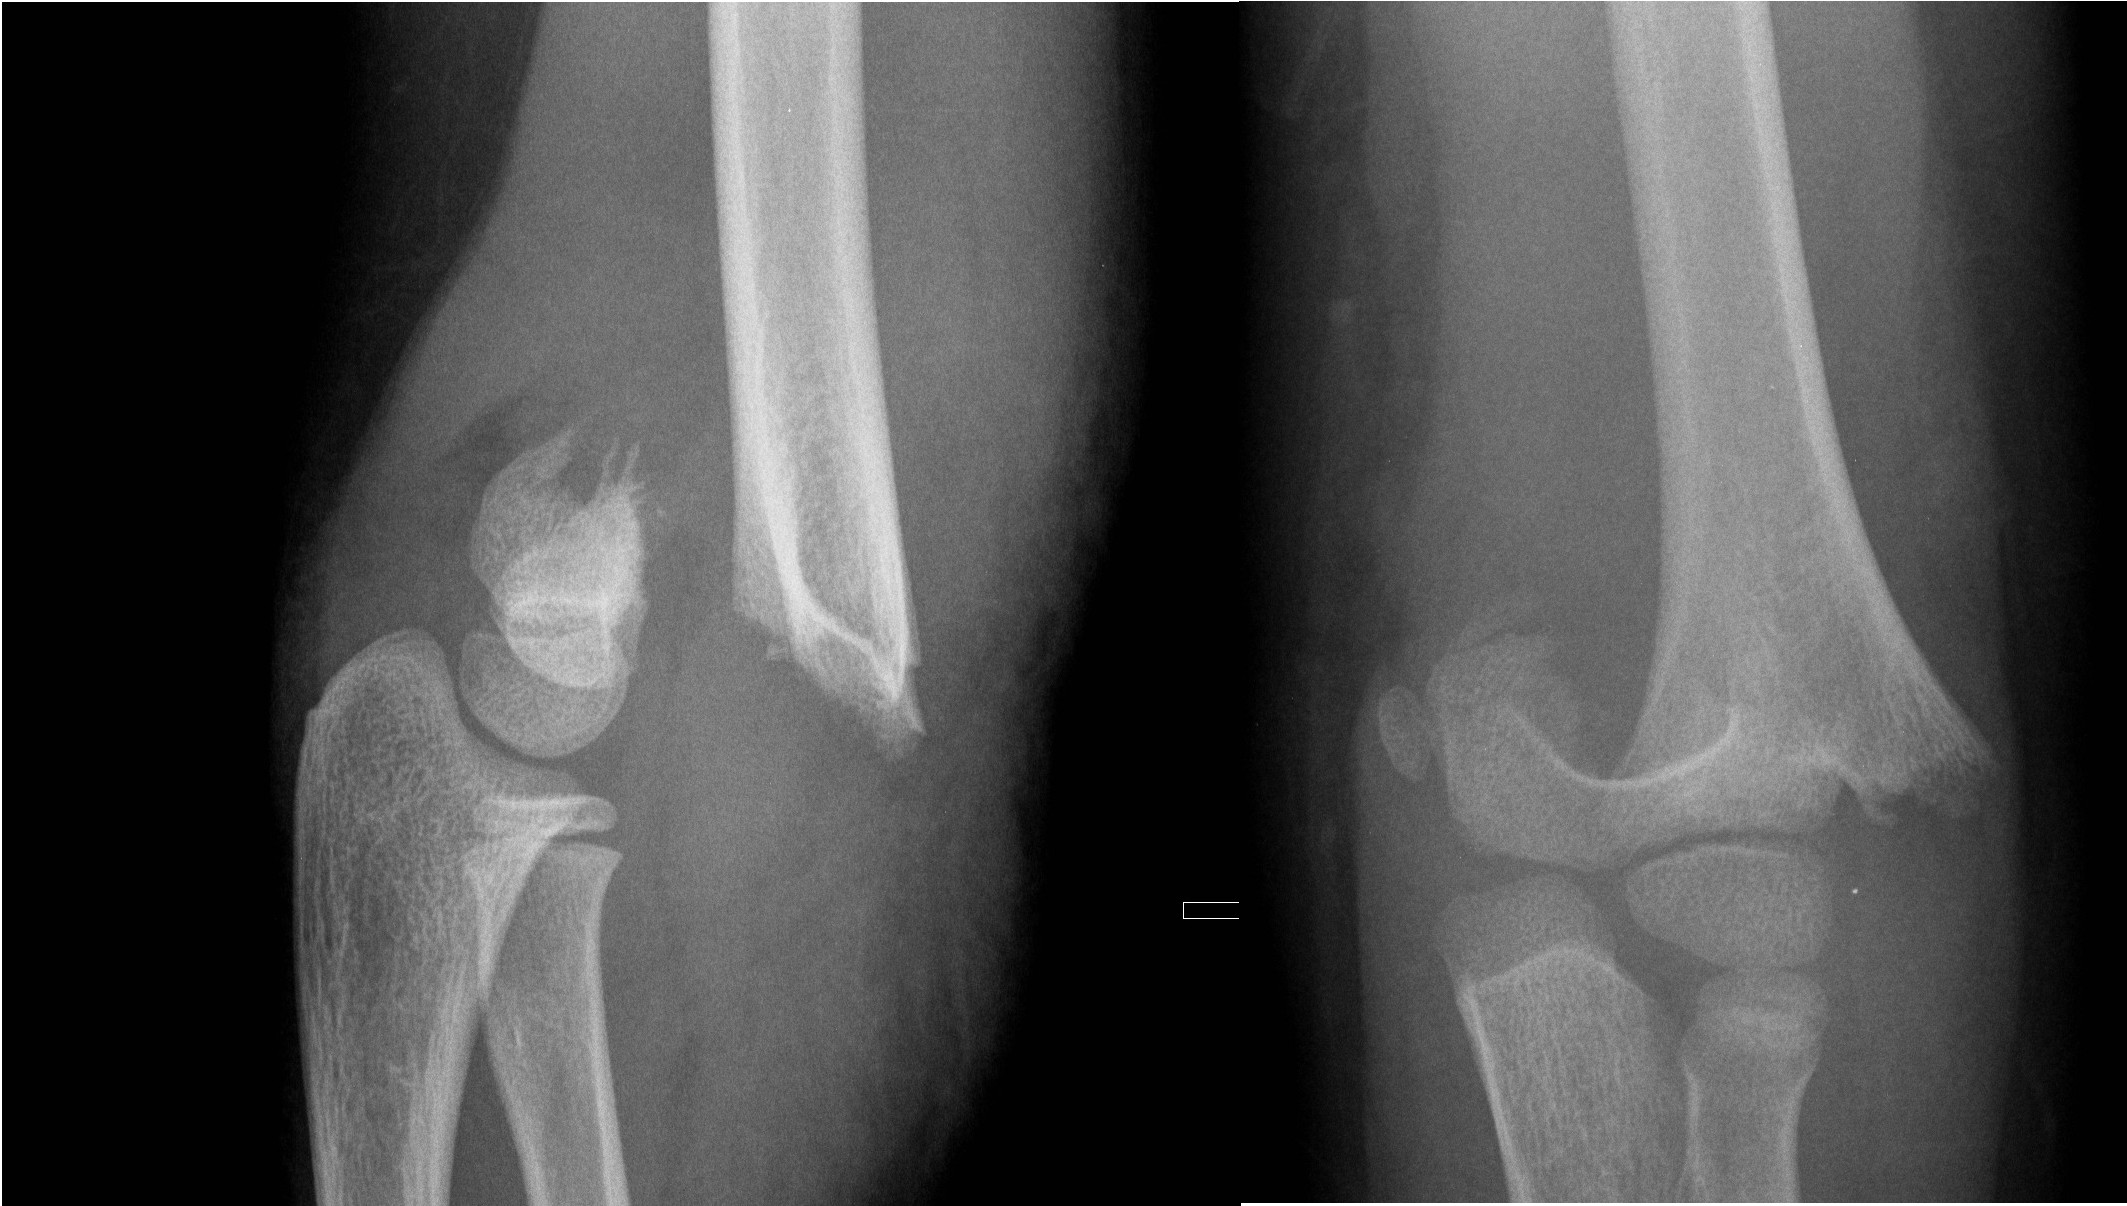

Off-ended supracondylar fractures (Gartland Type 3)

- High risk of neurovascular compromise.

- Requires urgent Orthopaedic review and open reduction and internal fixation (ORIF) in the operating theatre.

- If applying a resting slab in ED, plaster arm in current position. Do not flex elbow.

Displaced supracondylar fracture